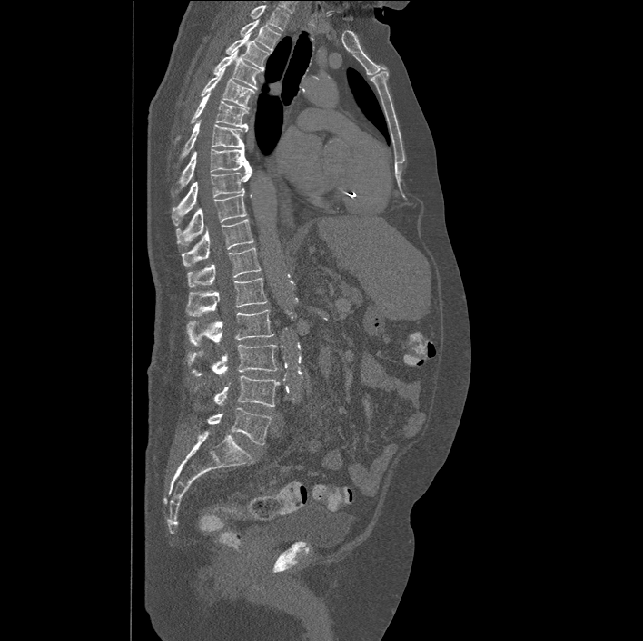

Spinal imaging via computed tomography (CT), magnetic resonance imaging (MRI), radiography, ultrasound, positron emission tomography (PET), and other radiologic imaging modalities is essential for noninvasively visualizing and assessing spinal pathology. Computational methods support and enhance a physician’s ability to utilize these imaging techniques for diagnosis, noninvasive treatment, and intervention in clinical practice. Analysis algorithms developed in the field of computer vision, computer graphics, signal processing, and machine learning have been adapted to analyze spinal images (Li et al., 2015). Conventionally, CT is preferred to study the spine due to a high bone-soft tissue contrast. There are diverse image appearance variations due to differences in vertebral position, metal artifacts and spinal diseases, etc., challenging the analysis algorithms. Fig. 1 gives some examples of these various conditions.

We calculate the two metrics of each vertebra, and the results are reported in Table 2. On the one hand, our experimental results are close to those reported in reference (Sekuboyina et al., 2020) with the same model (nnUnet), verifying the high quality of our annotations. On the other hand, Table 2 shows it is difficult to segment the diseased vertebrae (the DSC of L6 is almost 0). Specifically, the existence of L6 confuses the model, resulting in prediction dislocations (see the last row in Fig. 4). Thus, our labeled dataset, which contains many L6 cases, is very valuable for the diseased vertebrae segmentation (we have stated those cases that are hard for annotation in the readme.txt file). Table 2 illustrates that the model trained with our annotations can achieve good performance on our CTSpine1K dataset but a much worse performance on the VerSe Challenge datasets, which explains there is an obvious domain gap between our annotated dataset and the public dataset. We infer the reason is that the COlONOG dataset is based on an empty stomach and colon, confusing the deep learning model by the changes of air content in the abdomen (see Fig. 3). Therefore, our annotations are a good complement to the existing datasets.

3.2.2 Qualitative results.

Some visualization results are presented in Fig. 4, where we can observe that the baseline model can achieve excellent segmentation results. Nevertheless, some failed predictions occur when spinal diseases exist, especially sacral lumbarization and lumbar sacralization. Besides, the image’s resolution of Z direction is closely related to the results, and a lower resolution leads to worse results. Maintaining a reasonable performance for a low resolution is a research challenge. Image superresolution (Peng et al., 2020) might be worth exploring.